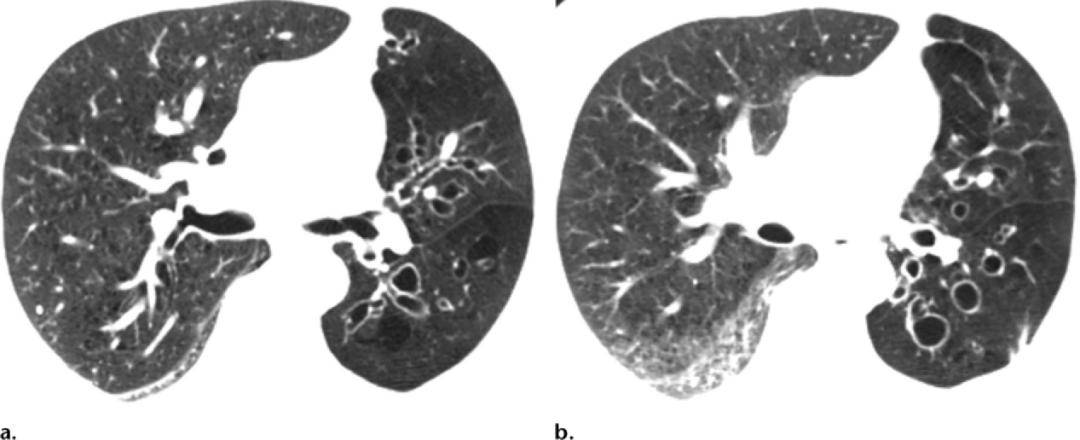

(a)就诊数天后横断面ct显示轻度柱状支气管扩张.